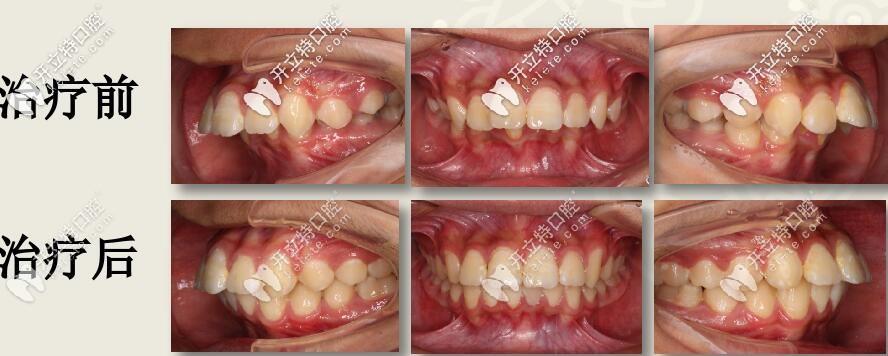

深復(fù)蓋凸嘴伴下巴后縮,直絲弓聯(lián)合擴(kuò)弓,斜導(dǎo)矯正27個(gè)月對比

12歲兒童齙牙,下巴后縮,牙列擁擠,全口直絲弓配合斜導(dǎo)、擴(kuò)弓器以及激動(dòng)器矯治,27個(gè)月后效果驚人。

今天西安圣貝牙科分享一例12歲兒童齙牙矯正案例,深覆蓋伴隨深覆合,采用雙期聯(lián)合配合肌激動(dòng)器矯治,矯治醫(yī)生是圣貝口腔何曉天醫(yī)生。

肉眼可見上前牙唇傾,輕度擁擠 下頜牙弓寬度窄,前牙區(qū)擁擠,后牙去舌傾明顯,前牙深覆蓋,深覆合

結(jié)束后,牙列整齊,深復(fù)蓋明顯改善。